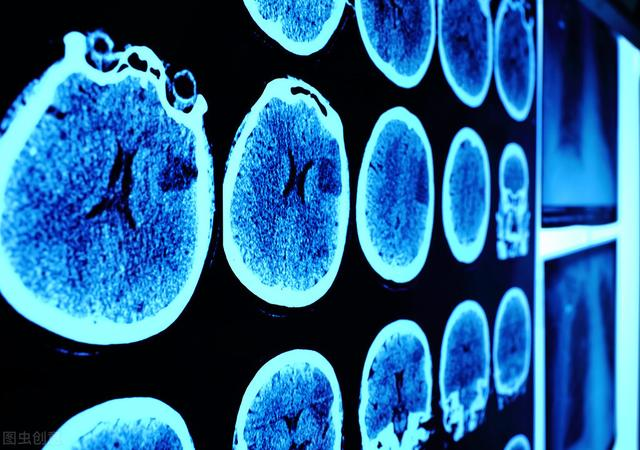

腔梗和脑梗的区别相关图片

640x480 - 34KB - JPEG

600x338 - 62KB - JPEG

640x450 - 483KB - PNG

420x243 - 29KB - JPEG

1201x589 - 48KB - JPEG

500x500 - 29KB - JPEG

640x401 - 31KB - JPEG

593x395 - 21KB - JPEG

293x371 - 16KB - JPEG

413x276 - 23KB - JPEG

640x597 - 59KB - JPEG

445x334 - 26KB - JPEG

448x252 - 33KB - JPEG

640x427 - 229KB - PNG

640x427 - 171KB - PNG